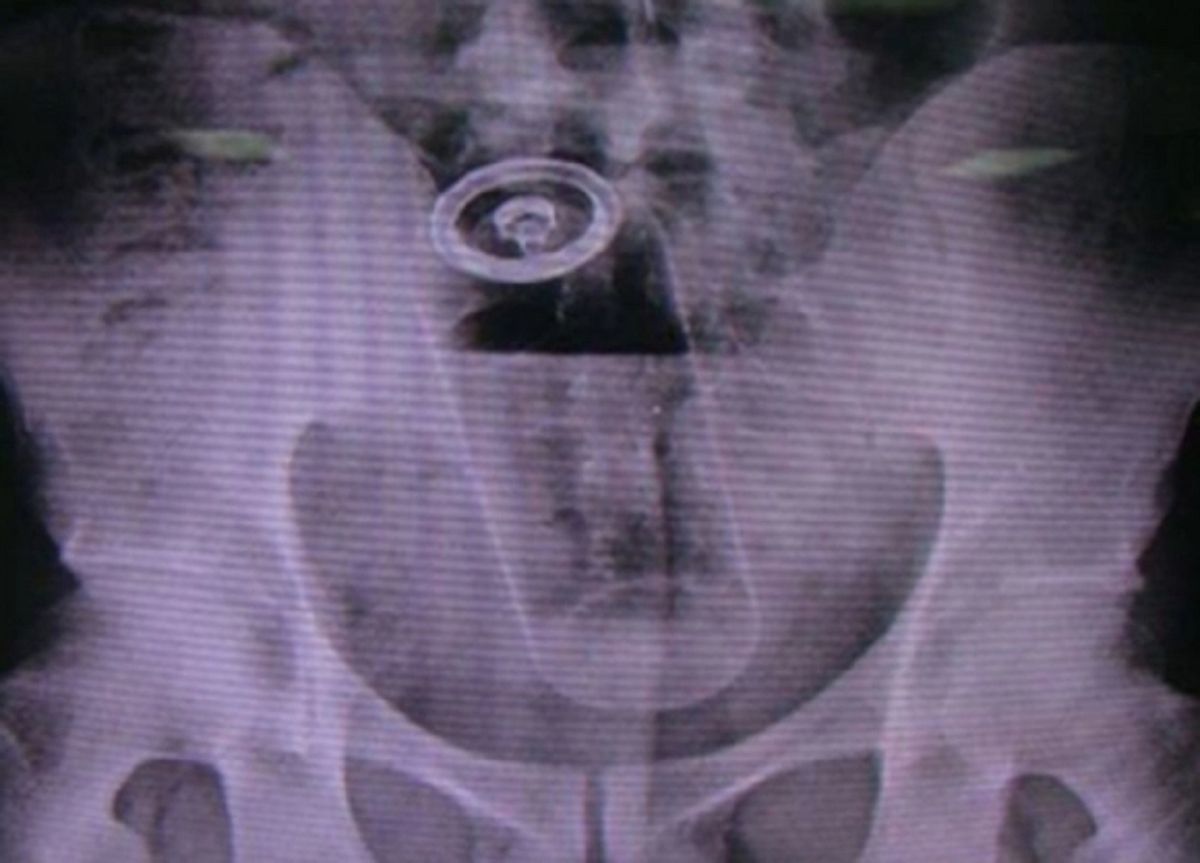

/ 8Słoik z kawą

Obraz

© imgur.com

Podobno pacjent był tak zawstydzony, że nawet nie próbował się tłumaczyć.